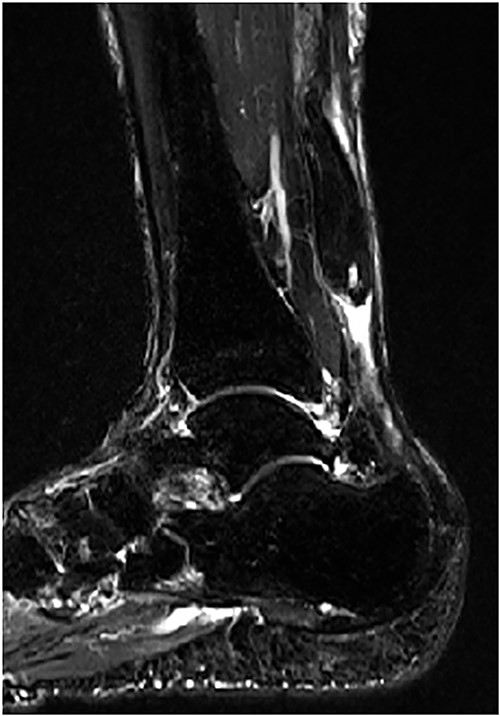

A 75-year-old male presented to a local clinic complaining of right heel pain after spraining his right ankle. He was diagnosed with an ankle sprain and treated conservatively for 2 months. However, the heel pain did not improve and so he visited our hospital. Physical examination revealed a palpable gap along the course of the Achilles tendon and a positive Thompson test. Plain radiographs showed no abnormalities, but MRI revealed a rupture of the Achilles tendon with a gap between the tendon ends (Fig. 3). Based on physical examination and imaging findings, we diagnosed the patient with chronic ATR and administered surgical treatment.